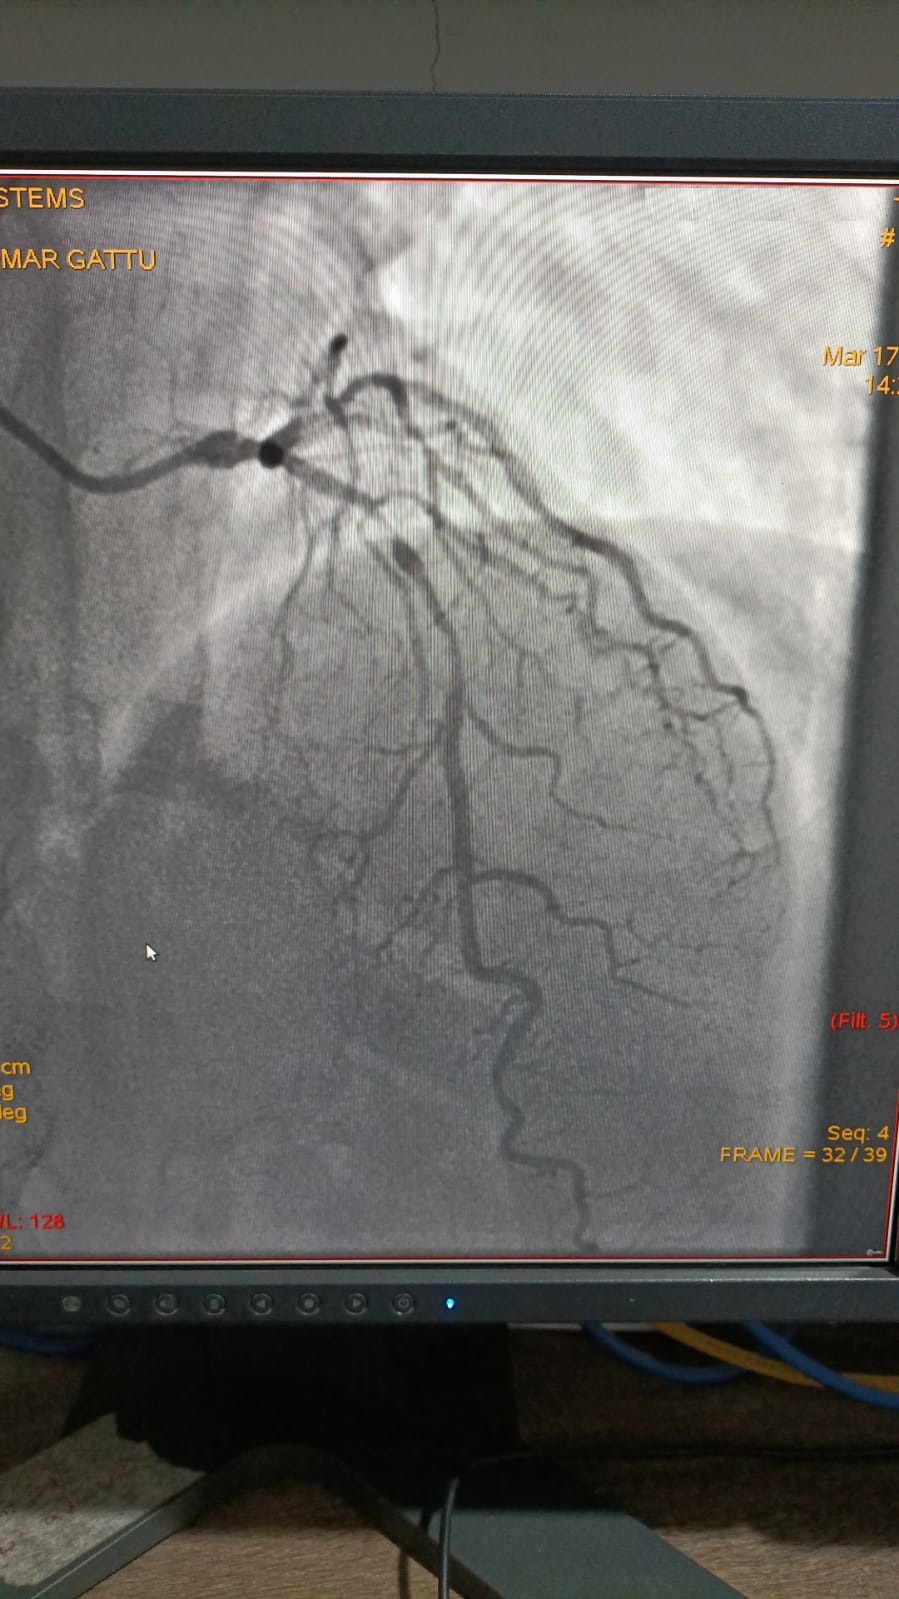

Left Coronary Artery